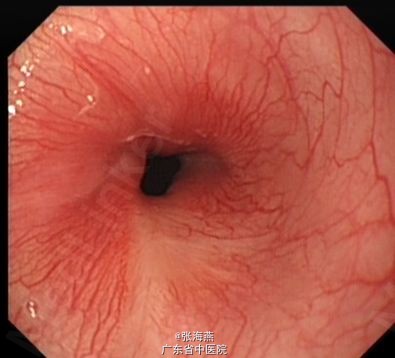

随访及讨论:患者2013年9月4日复查胃镜提示食管粘膜愈合良好,可见疤痕存在,管腔无狭窄,患者进食通畅,无不适感。对于此巨大平滑肌瘤,内镜成功切除,可避免患者开胸手术,大大提高了患者生活质量。